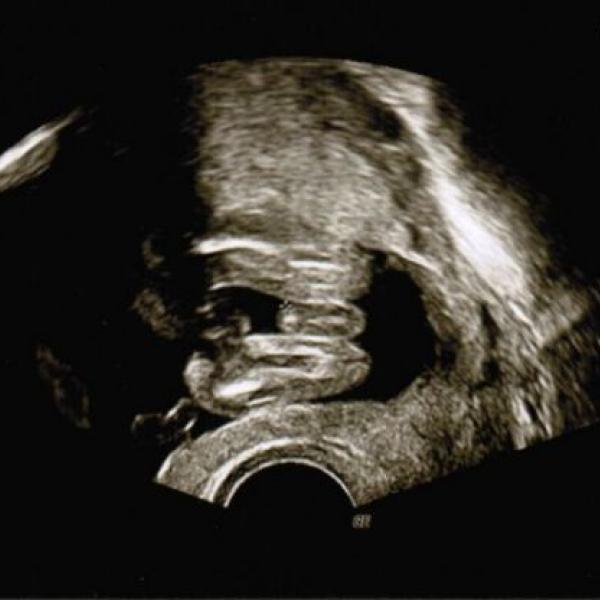

Oliva cerna 07.10.2011 Detail co myslíte, je to chlapeček? :) Komentáře jsou momentálně nedostupné. Děkujeme za pochopení. Oliva cerna 14.07.2011 Detail Dnešní první kontrola 4+6tt, zatím není moc vidět, přesto radost velikááá :) kontrolu máme za týden :) Komentáře jsou momentálně nedostupné. Děkujeme za pochopení.